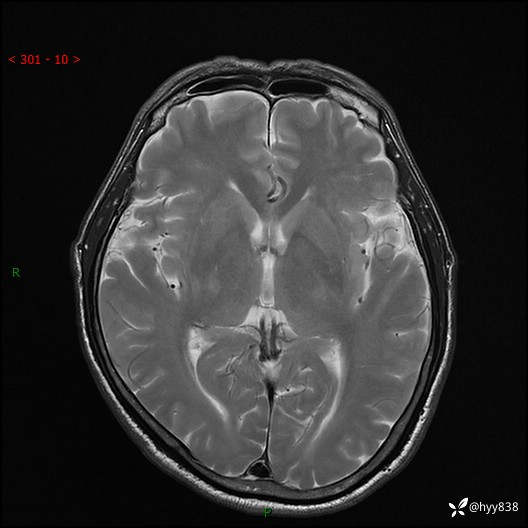

颅脑MRI平扫